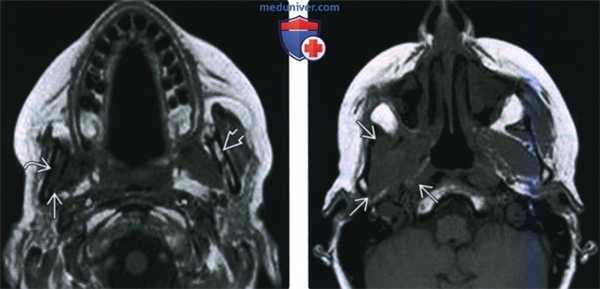

(Слева) МРТ Т2ВИ FS, аксиальная проекция. Наблюдается повышенная интенсивность сигнала крыловидных мышц и глубокой части височной мышцы. Затемнение ячеек сосцевидного отростка говорит о дисфункции слуховой трубы вследствие паралича мышцы, напрягающей небную занавеску. У этого пациента была обнаружена менингиома, локализующаяся в тройничной полости (здесь не отображена).

(Справа) МРТ Т1ВИ FS с КУ, коронарная проекция, этот же пациент: умеренное накопление контраста в крыловидных мышцах и уменьшение в размерах трубного валика. Такие находки говорят о подострой денервационной атрофии нижнечелюстного нерва. (Слева) МРТ Т1ВИ, коронарная проекция. Хроническая жировая атрофия левой височной и жевательной мышц? которая говорит о хроническом повреждении нижнечелюстного нерва. По сравнению со здоровой стороной левая челюстно-подъязычная мышца также уменьшена в размерах, имеется незначительная жировая инфильтрация.

(Справа) МРТ Т1ВИ в аксиальной проекции, этот же пациент. Правая челюстно-подъязычная мышца и подкожная мышца шеи интактны. Их отсутствие/сильная атрофия слева говорят, что повреждены и нижнечелюстной (челюстно-подъязычная мышца), и лицевой (подкожная мышца шеи) нервы.